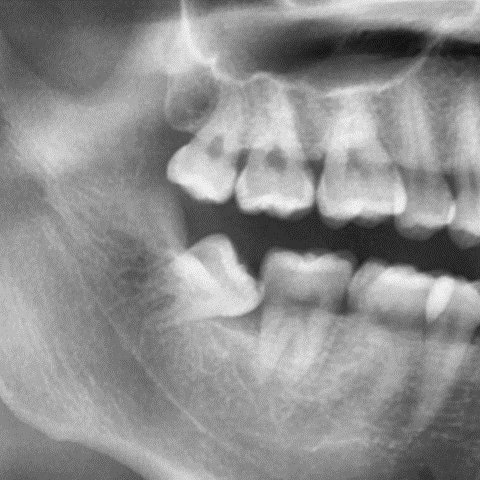

2024. 9 첫 내원 당시 파노라마 사진

오른쪽 아래 사랑니가 옆으로 누워있는 형태인 매복 사랑니였는데요.

이런 위치의 경우 관리하기가 쉽지 않고,

통증, 잇몸 염증(붓기), 치아 우식이 발생하기 쉽기에

가급적이면 더 나빠지기 전에 발치하시는 것을 권유 드리는 편입니다.